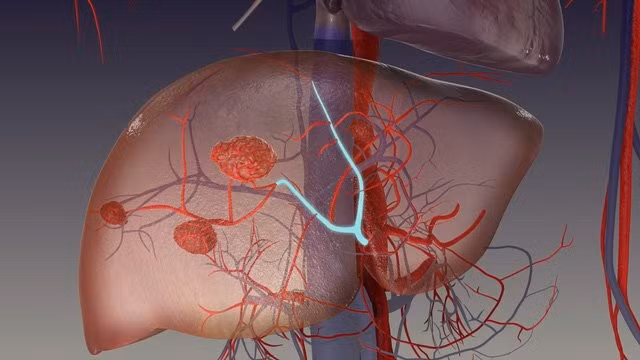

Khi u máu gan gây ra triệu chứng nghiêm trọng hoặc có nguy cơ biến chứng như chảy máu, phẫu thuật cắt bỏ khối u có thể được thực hiện. Thuyên tắc mạch thường được áp dụng cho những bệnh nhân không đủ điều kiện sức khỏe để phẫu thuật hoặc có nhiều khối u nhỏ.

Một số thuốc có thể được sử dụng để làm giảm kích thước của u máu gan hoặc kiểm soát triệu chứng. Các loại thuốc này có thể bao gồm thuốc ức chế mạch máu hoặc các loại thuốc giảm đau để kiểm soát các triệu chứng liên quan.

Ghép gan là phương pháp cuối cùng, hiếm khi được áp dụng, chỉ dành cho những trường hợp u máu gan rất lớn hoặc khi các phương pháp điều trị khác không hiệu quả, khối u gây suy gan nghiêm trọng.

Việc lựa chọn phương pháp điều trị u máu gan phụ thuộc vào nhiều yếu tố như kích thước, vị trí của khối u, triệu chứng mà bệnh nhân gặp phải và tình trạng sức khỏe tổng thể của người bệnh. Thảo luận với bác sĩ chuyên khoa là điều quan trọng để xác định phương pháp điều trị phù hợp nhất.